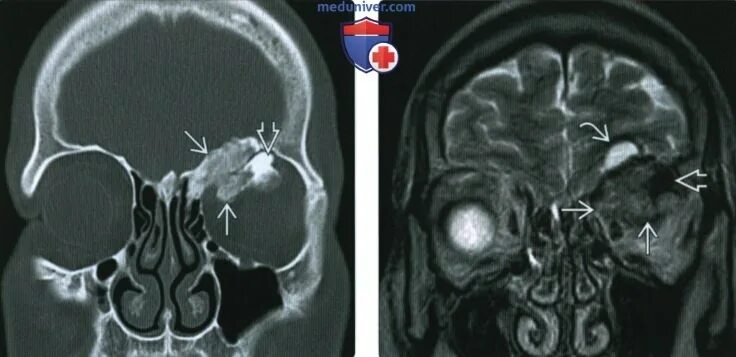

Остеома мрт